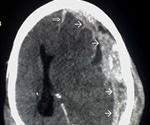

How is Shaken Baby Syndrome Diagnosed?